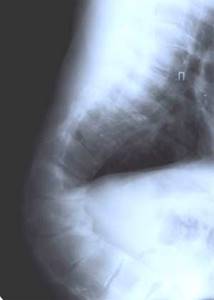

| Больная Л-ч, 12 лет сколиоз IV степени |

Результат оперативного лечения |